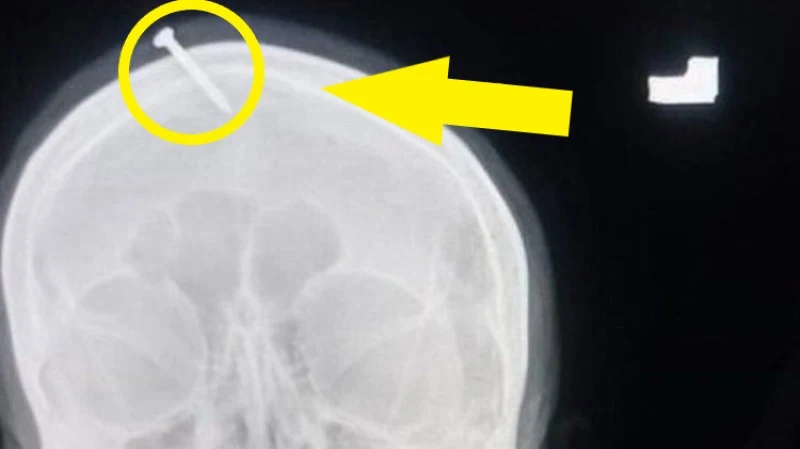

Lekarze z pakistańskiego szpitala Lady Reading w Peszawarze nie dowierzali, gdy usłyszeli historię pewnej ciężarnej kobiety, która przyszła do nich z gwoździem wbitym we własną czaszkę. Jak się okazało, taką praktykę zalecił jej lokalny uzdrowiciel, gwarantując jej, że po takim czynie z pewnością urodzi upragnionego syna. Wcześniej Pakistanka już trzykrotnie rodziła, doczekując się trzech córek.

Z olbrzymim bólem kobieta trafiła do szpitala. Wcześniej próbowała jeszcze sama usunąć gwoździa ze swojej głowy, jednak bezskutecznie. Na szczęście nie dostał się on do mózgu i nie spowodował poważniejszych uszkodzeń, a lekarze zdołali go wydostać.